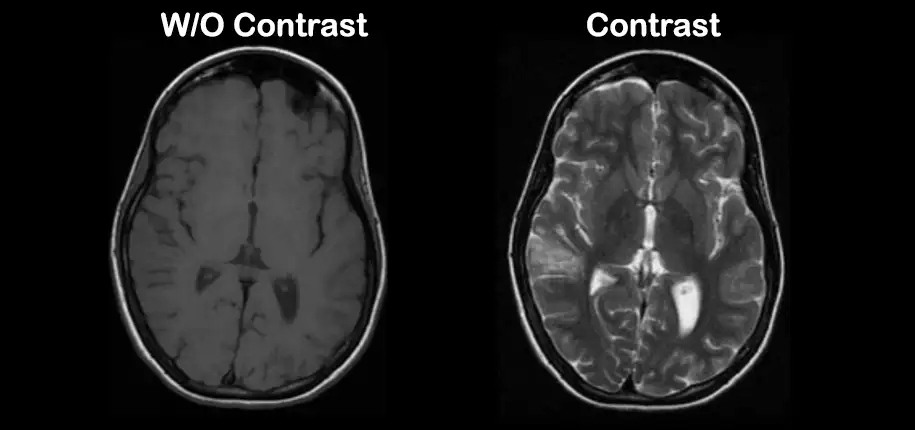

You might have learned from previous radiology blog articles that gadolinium is an element that is used in MRI contrast. MRI contrast is a medicine that is injected into the veins. The contrast allows our radiologists to better visualize any abnormalities within the body. Some things show up on scans that we’d otherwise be unable to see without using contrast. Here at Cincinnati Children’s, our radiologists are very careful in only using IV contrast when it is truly necessary for the exam.

New to the gadolinium family is a contrast called Elucirem. We are excited to utilize this new product at Cincinnati Children’s for several reasons: A lot of research and testing has been done to show that Elucirem is even more stable than Dotarem, meaning it is less likely to leave any metal remnants within the body. Elucirem has a high relaxivity, or sensitivity. This means that it has half the amount of gadolinium, but it enhances just as much. In fact, radiologists have noticed that abnormalities highlight even brighter than before! Elucirem has the same low risk of reactions as Dotarem. What a wonderful breakthrough! We get the same effect while administering half the amount of contrast.